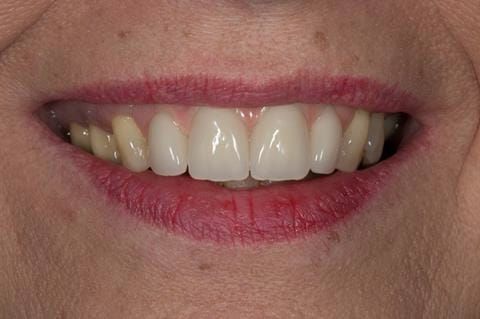

- High smile line showing gum above gingival zeniths of upper front teeth when smiling. Aesthetic failure of the upper four incisors with inflammation of the gingivae and mis-match of the gingival zenith levels.

- Extract the upper 2-2 teeth and replace with an interim acrylic based partial denture. Reline the interim denture over 9 - 12 months, replacing with a definitive cobalt chromium based partial denture. The definitive denture would ideally be designed as an occlusal protective splint to reduce the the potential for mechanical wear and breakages of the moderately/heavily restored maxillary dentition. In addition, should further upper teeth require extraction they could be added on to the denture cobalt chromium framework - therefore a new prosthesis would not be required as future teeth are lost. This option would produce an excellent aesthetic outcome. This is the option the patient chose to have.

Following consultation and second discussion appointment the patient chose to have option 3 namely, a maxillary cobalt chromium based partial denture/protective occlusal splint. The clinical situation and treatment process is shown in detail below with photographs. The patient was successfully rehabilitated with this and her quality of life considerably improved. The clinical work was provided by Finlay and the technical work by Rowan.